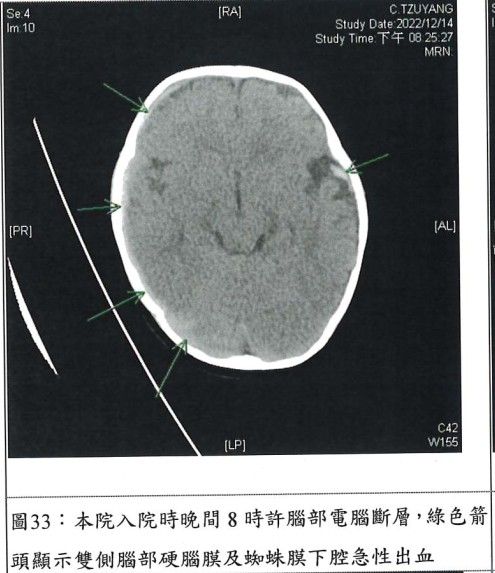

不過,男嬰經診斷後,發現他腦部及視網膜嚴重出血,還有癲癇症、無意識狀況等,而腦傷也導致其左側肢體無力、水腦症、眼部及眼底出血及右腦神經「永久性」損傷。